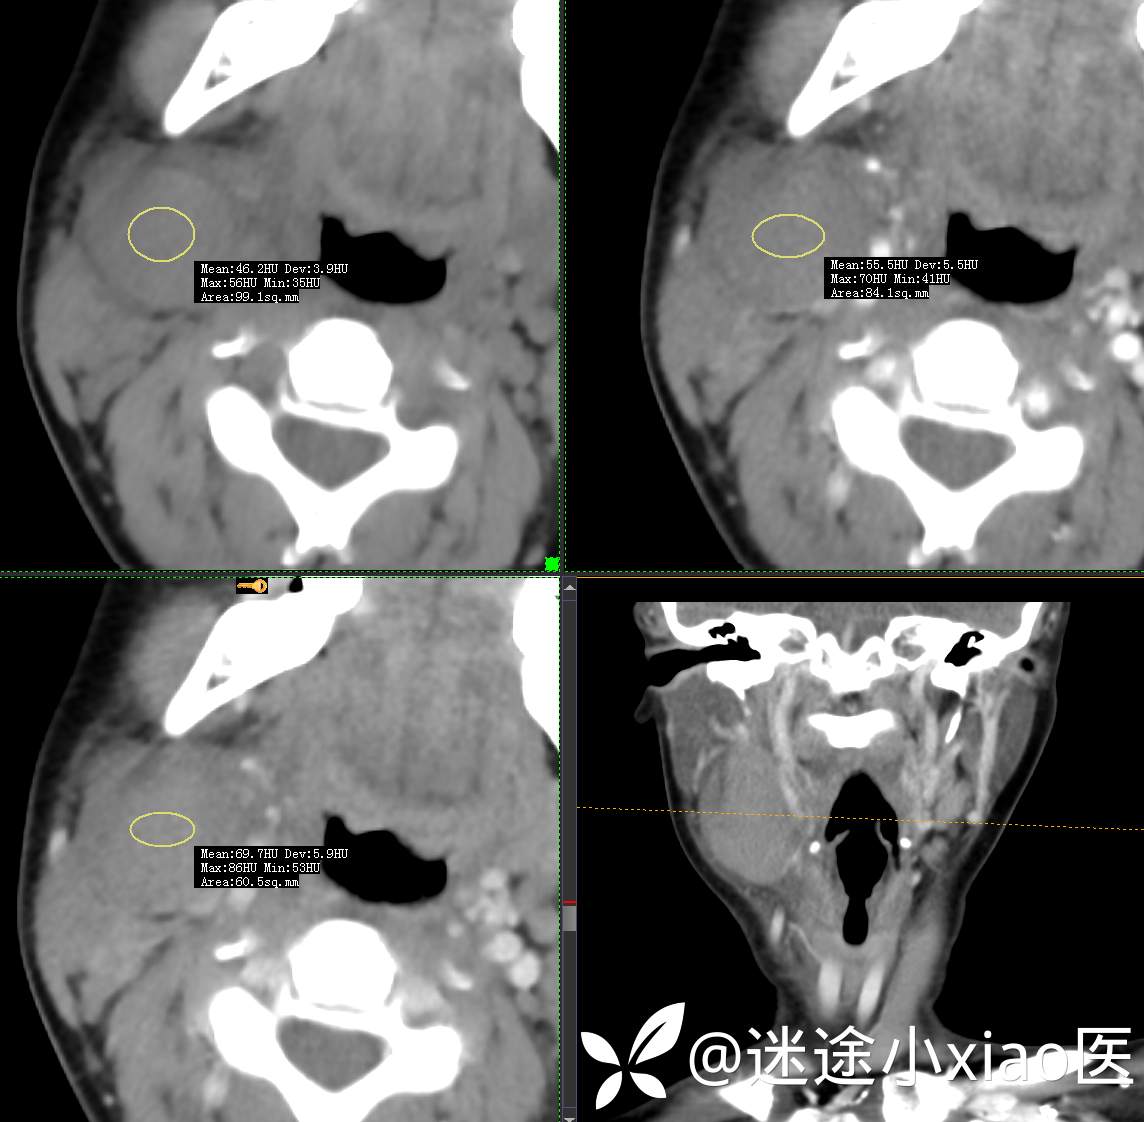

头颈组16:青少年女性,发现右颈部肿物半月余,感染?肿瘤?

主 诉:发现颈部肿物半月余

现病史:患者半月余前无明显诱因下发现右颈部肿物,大小4.2*2.1cm,局部无红肿,皮温正常,有压痛,感头晕头痛,无其他不适。查甲状腺及颈部淋巴结B超提示:双侧甲状腺多发结节;右侧多发肿大淋巴结。初步诊断为“淋巴炎”,予“头孢类”抗生素抗感染治疗12天(具体药物不详),自觉肿块胀痛缓解,头晕头痛症状仍存。